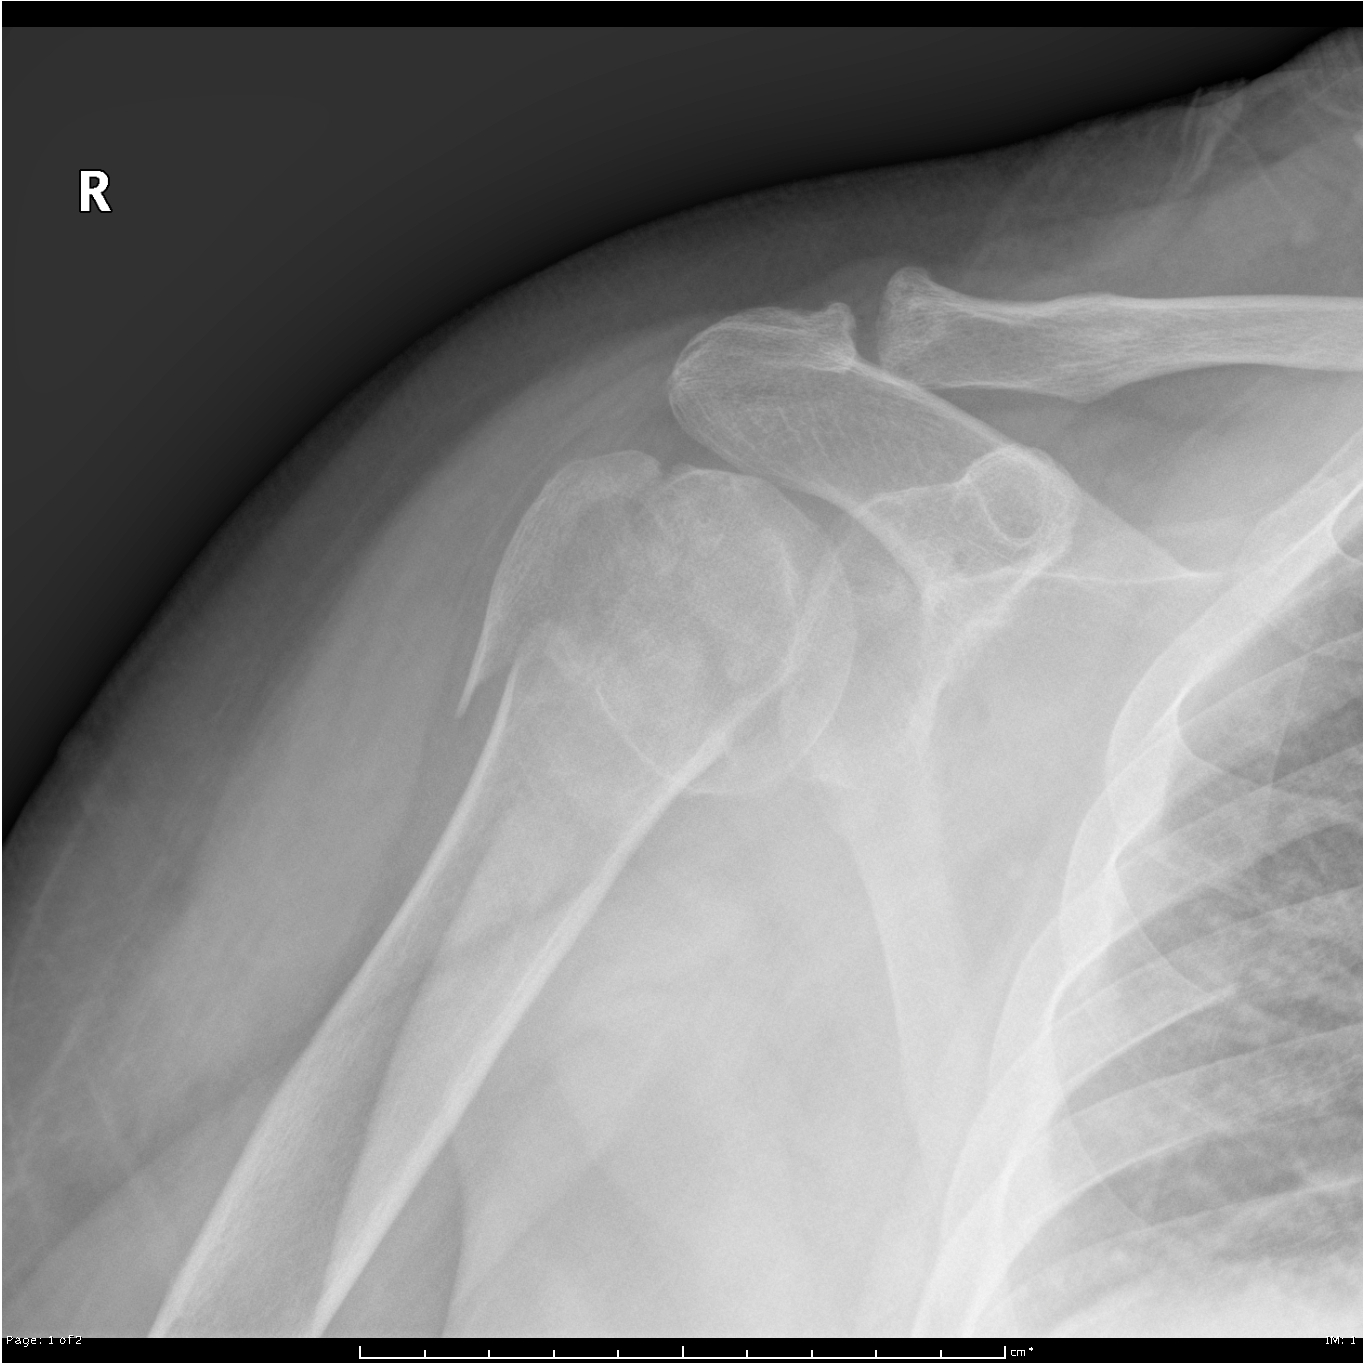

Beschreiben Sie die Befunde auf dem vorliegenden Röntgenbild der Schulter.